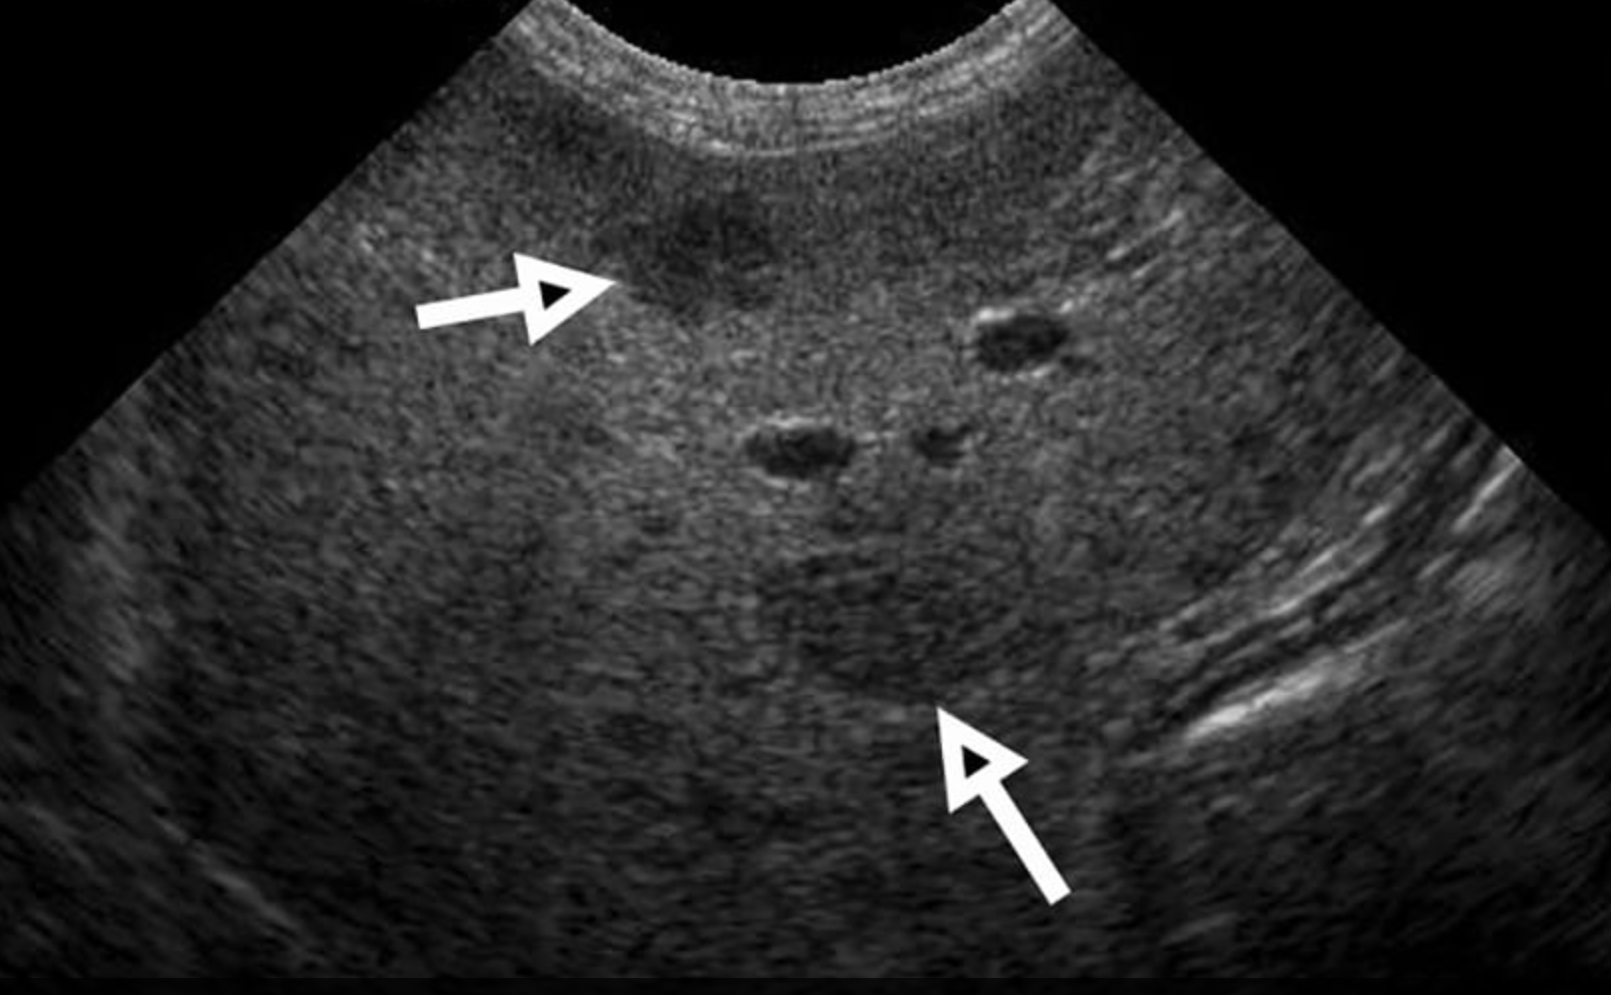

Which of these liver masses/nodules is a malignant tumor.

B-mode ultrasonography is highly sensitive for detecting focal liver lesions but is poorly specific for lesion type. Hepatic masses may appear:

• Hypoechoic, hyperechoic, or mixed echogenicity

• Well-marginated or irregular

• Solitary or multifocal

Importantly, echogenicity does not correlate reliably with malignancy. Multiple studies have demonstrated substantial overlap in the sonographic appearance of benign nodules, primary hepatic tumors, and metastatic lesions (Nyland et al., 2002; O’Brien et al., 2004)

In a large retrospective study of canine liver tumors, no consistent B-mode ultrasonographic features reliably differentiated hepatocellular carcinoma, cholangiocarcinoma, sarcoma, or metastatic lesions, aside from lesion distribution (O’Brien et al., 2004). Hepatocellular carcinomas were more likely to be solitary, whereas sarcomas and metastases were more often multifocal, but significant overlap existed.

Conclusion

Ultrasonography is indispensable for detecting and characterizing liver masses in dogs, but its diagnostic specificity is limited. Neither B-mode imaging, Doppler, CEUS, nor elastography can consistently differentiate benign from malignant lesions. Metastatic disease is more common than primary hepatic neoplasia, and benign nodules are extremely prevalent in older dogs. Consequently, imaging findings must be interpreted cautiously, and cytologic or histopathologic sampling should be recommended in the majority of cases to achieve a definitive diagnosis.

Correct answer